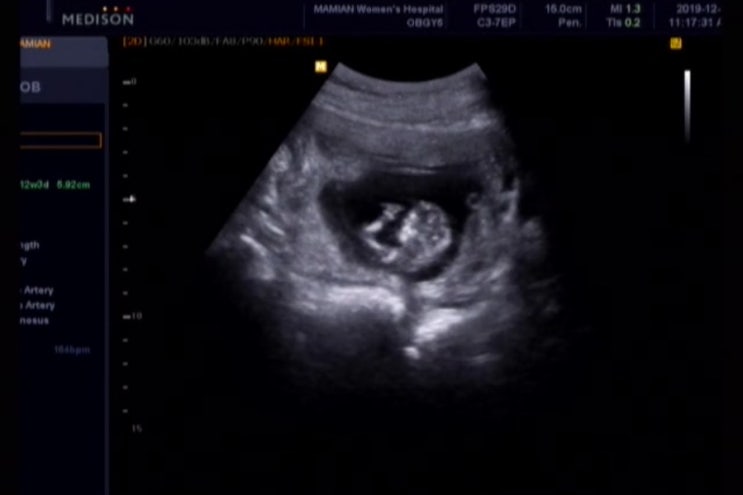

[임신 기록 : 첫찌] 12주 16주 20주 임신 기록. 기형아 검사 완료

5년 만에 쓰는 장꼬맹의 임신 기록, 초음파 사진과 세이베베 동영상으로 보니, 그때 기억이 조금씩 나기 시...

[임신 기록 : 첫찌] 아기집 확인부터 10주차 까지. 태아 목투명대 확인

장꼬맹이 태어난지 벌써 1630일째 . 이제서야 남겨보는 장꼬맹 임신기록. 장꼬맹을 처음 만난날은 19년 11...